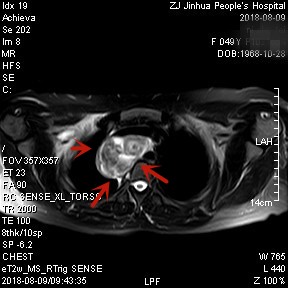

上图均示MRI下的肿瘤情况,红色箭头示肿块